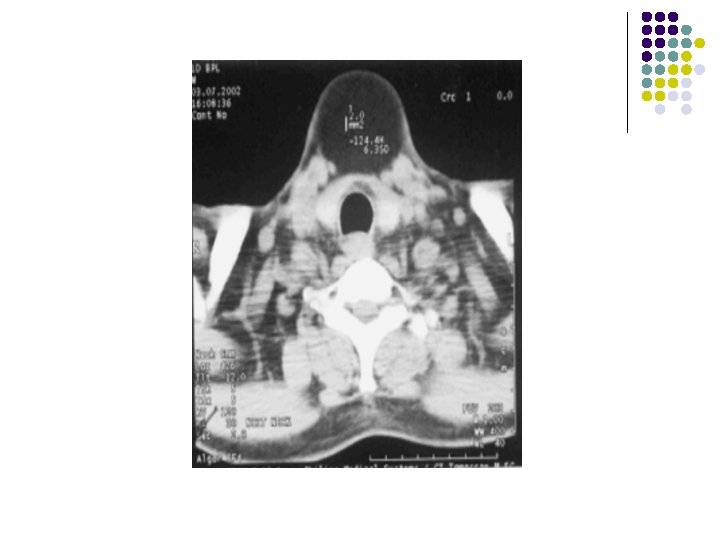

CASE 2 l A 17 YEARS OLD FEMALE PRESENTED WITH PAINLESS ANTERIOR MIDLINE NECK MASS. O/E: l Swelling moves on deglutition and on protrusion of tongue.

FINDINGS: sagittal ultrasound image (left is superior) shows a cystic anechoic structure just below the level of the hyoid bone. A small beak of the cyst can be seen passing superiorly over the hyoid.

Findings: l Soft tissue density lesion in midline below the level of hyoid bone embedded within the strap muscles.

l Thyroglossal duct cysts develop anywhere along the course of the duct remnant, from the base of the tongue to the suprasternal region. l Frequently located in the region of the hyoid bone. l Cysts located above the level of the thyroid cartilage are usually midline, while cysts located below the level of the thyroid cartilage are off midline. l Presents as an asymptomatic, mobile mass in the anterior triangle of the neck WHICH MOVES ON DEGLUTITION AND ON PROTRUSION OF TONGUE. l Patients present in their teens or twenties because of enlargement and/or infection.

IMAGING FEATURES: l On ultrasound, they appear as hypoechoic masses with few septae and internal echoes. l CT scan : They are hypodense and well defined with minimal enhancement of the margins on contrast scans. l MR can also be used for superior soft tissue evaluation. The lesions are hypointense on T 1 W images and hyperintense on T 2 W images. l l These lesions usually lie medial to the sternocleidomastoid muscle, anterior to the carotid sheath and lateral to the thyroid gland.

IN OUR PATIENT… l l Midline ant. Neck mass which moves on protrusion of toungue. Anechoic cystic lesion in infrahyoid region with beak extenmding in suprahyoid region on usg. on. Ct. . Low density lesion with mininmal rim enhancement and in classical location. DIAGNOSIS: THYROGLOSSAL CYST